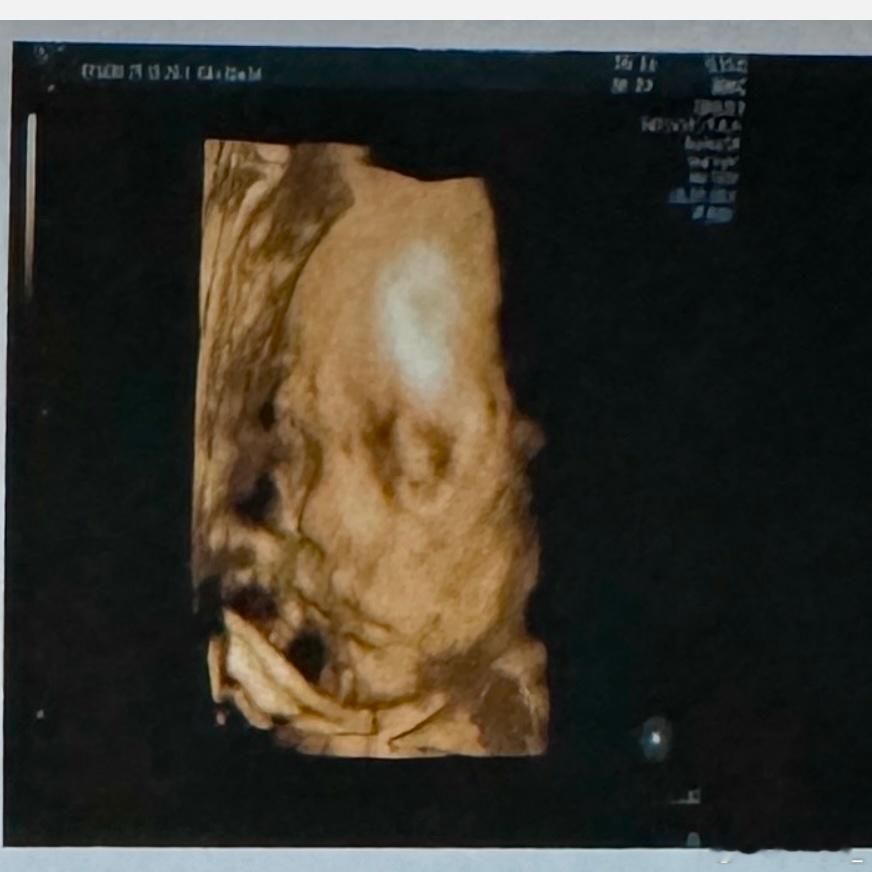

宝宝的鼻子生的真好看又被医生夸了[爱慕][爱慕]

宝宝的鼻子生的真好看

又被医生夸了[爱慕][爱慕]